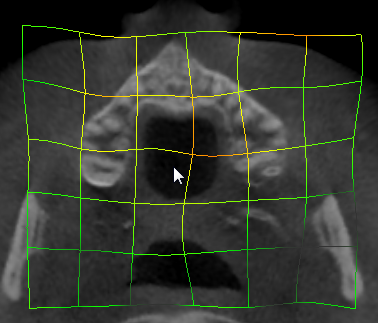

Import the sample microCT stack (or load the NRRD, if you already saved it) into a blank scene. Switch to the Transforms module

- Put the volume under a blank transform and try using the rotation sliders to change the slice views. Explore other options of the transform module. See that if you remove the 3D volume out of the transformation, slice views go back to original orientation